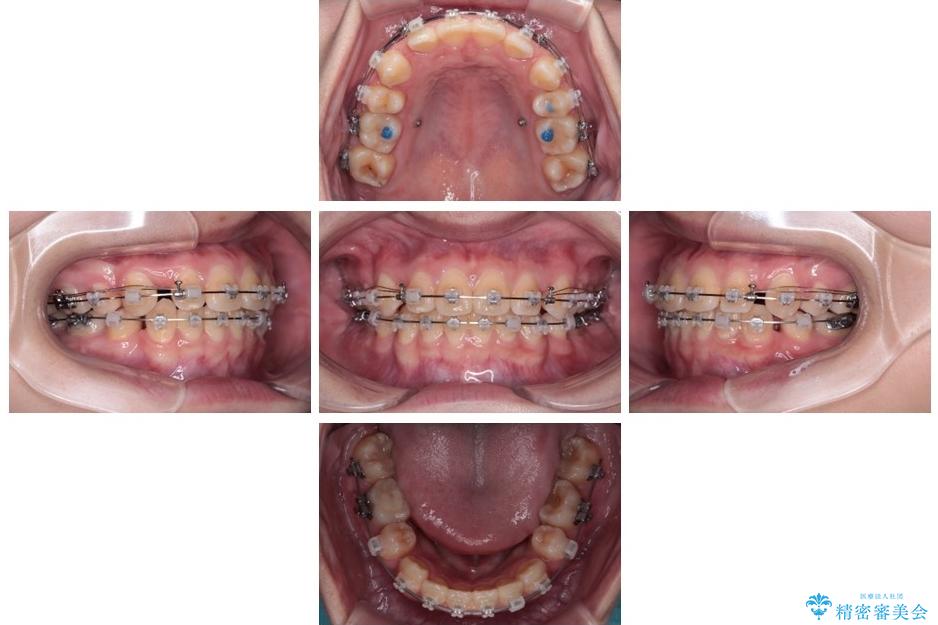

治療後

• 転勤でも安心して治療継続 抜歯スペース閉鎖と深い噛み合わせ改善のワイヤー矯正 治療後画像

結果的に1年半で、再度転勤になる前に治療を終えることができました。